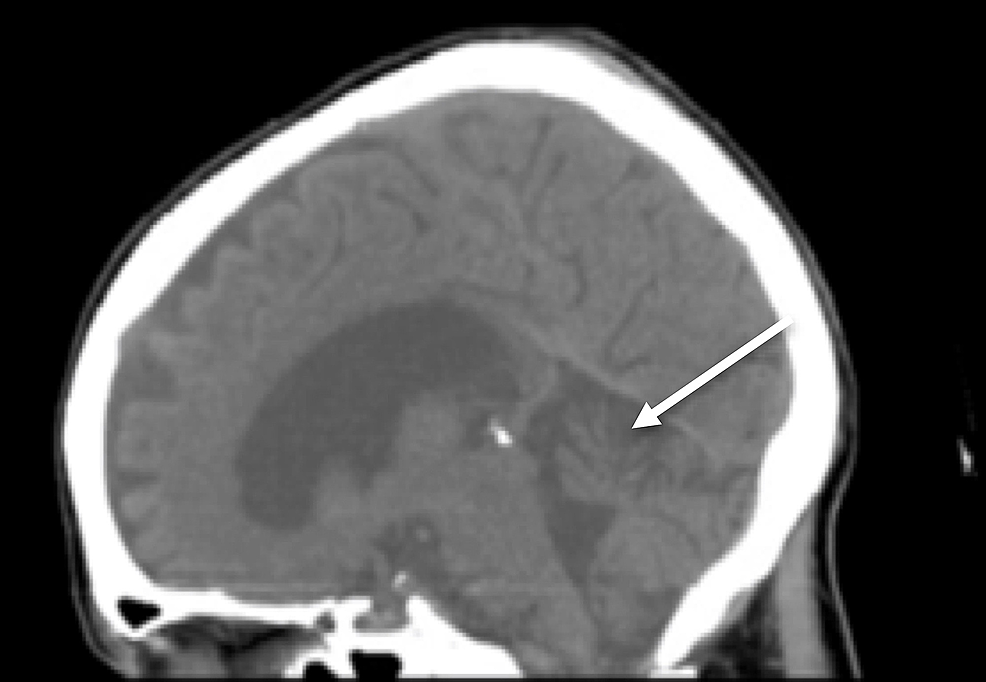

A CT of her brain revealed cerebellar vermian atrophy but was otherwise unremarkable (Figure 1).

MRI of her brain demonstrated cerebellar volume loss, increased FLAIR signal in the cerebellar vermis, normal corpus callosum and normal mammillary bodies (Figures 2-7).

Although not required for a diagnosis of acute WE, “typical” MRI findings include hyperintense FLAIR/T2 signal in the thalami, mammillary bodies, tectal plate, periphery of the third ventricle, and periaqueductal area [3,6]. Approximately 50% of patients with WE exhibit “atypical" MRI findings including FLAIR/T2 hyperintensity in the superior cerebellum, cranial nerve nuclei, red nuclei, dentate nuclei, caudate nuclei, splenium, and cerebral cortex [6]. Historically, these “typical” findings were thought to be more associated with alcoholics while the “atypical” findings were more associated with non-alcoholics. However, recent literature suggests that “typical” and “atypical” findings are less closely linked to alcohol-related and non-alcohol related WE than previously reported, as in our patient with alcohol-related WE displaying only “atypical” MRI features [7]. Differential diagnosis in patients with MRI findings of WE would include arterial/venous infarction (expected to show restricted diffusion), viral encephalitis (expected to have greater areas of increased FLAIR/T2 signal; atrophy would be unusual) and Marchiafava-Bignami Disease (expected to have callosal signal abnormality).